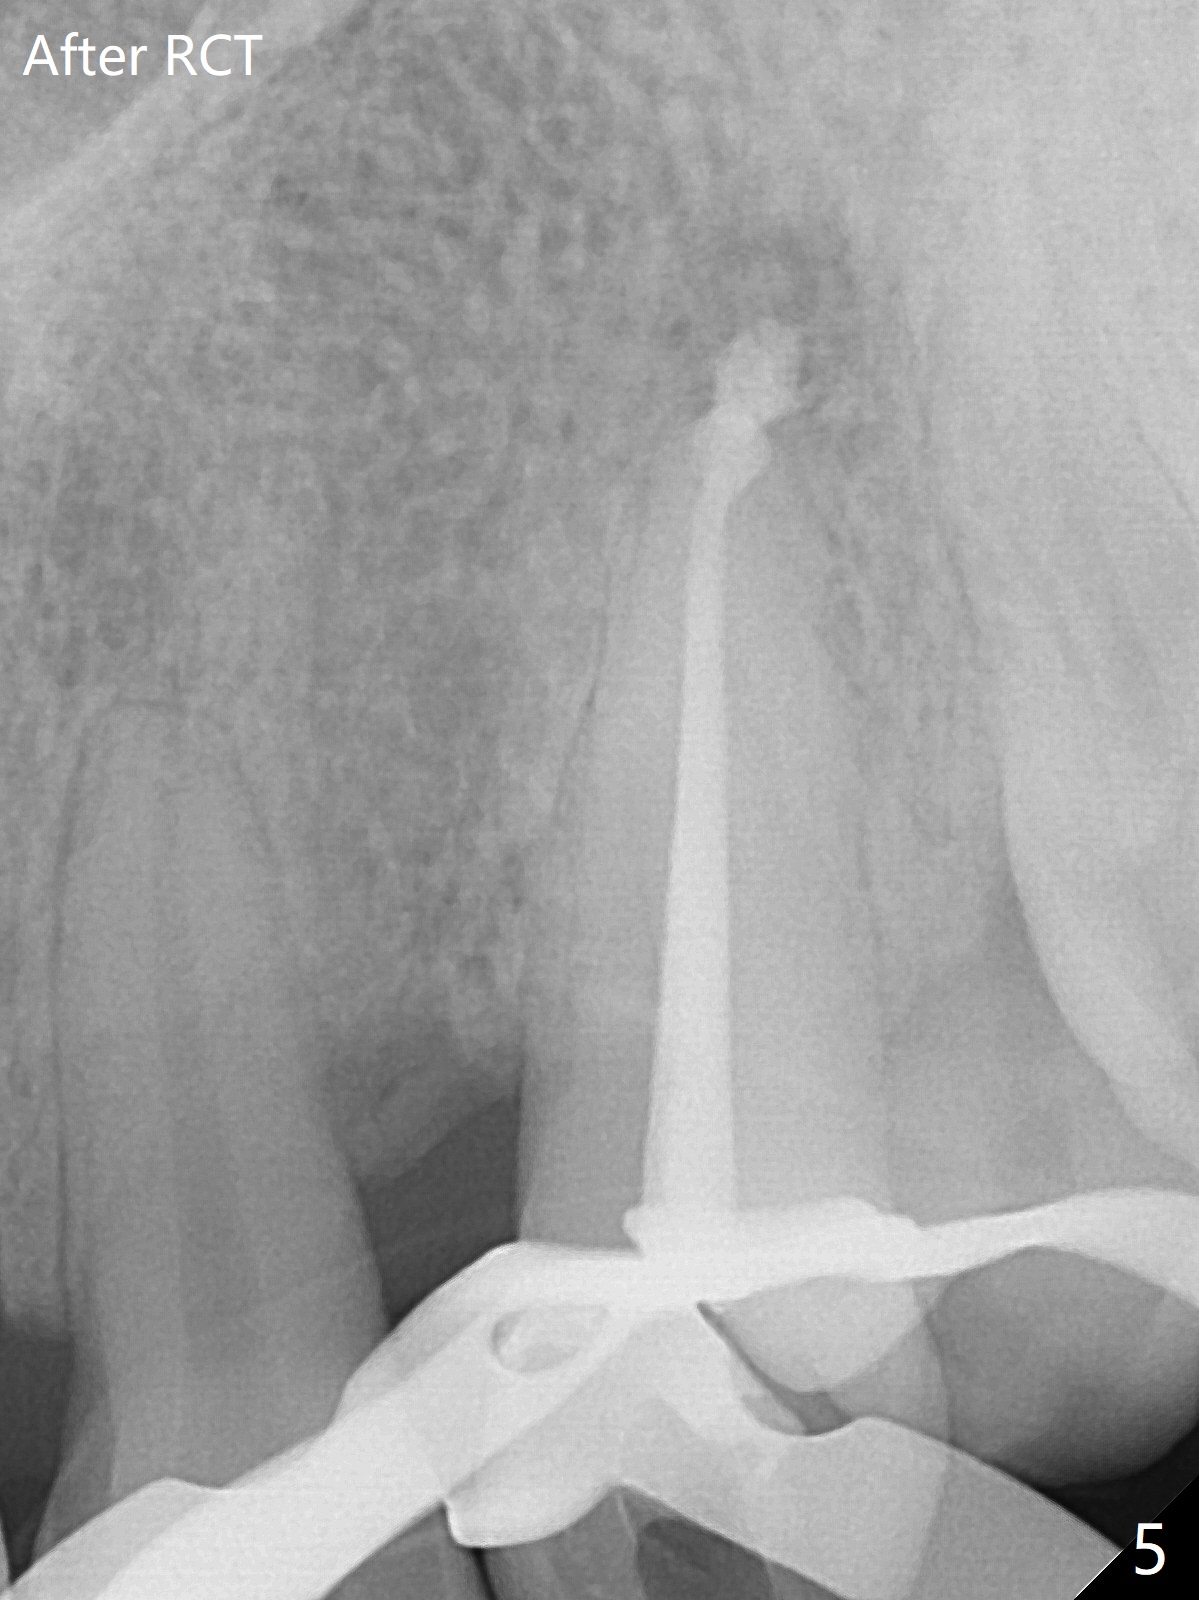

A 45-year-old man had severe malocclusion and chose non-extraction orthodontic treatment (Fig.1 (2012)). Five years later, the tooth #11 discolors (Fig.3, as compared to #6 in Fig.2). Immediately after RCT (Fig.4,5), the affected tooth has sudden change in shade (Fig.6). Two weeks later there is rebound in shade (Fig.7). The latter improves after two rounds of chair-side internal bleaching with 35% Hydrogen Peroxide for 20 minutes and build-up with the lightest shade composite (Fig.8). For optimum, place the bleach gel in the pulpal chamber and close the access with Cavit for a few days. In fact the latter is unnecessary. The treated tooth looks as normal as the tooth on the other side 1 year 10 months post whitening (Fig.9). PARL reduces 3 years post RCT (Fig.10 <, as compared to Fig.5).